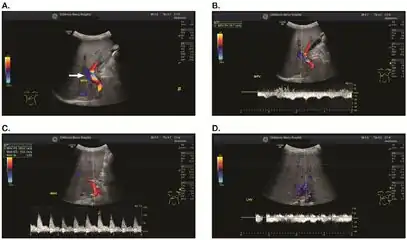

Doppler ultrasound of the liver is typically utilized to confirm or suggest the diagnosis. Common findings on liver doppler ultrasound include increased phasicity of portal veins with eventual development of portal flow reversal.

The liver is usually enlarged but maintained normal echogenicity. A liver biopsy is required for a definitive diagnosis.